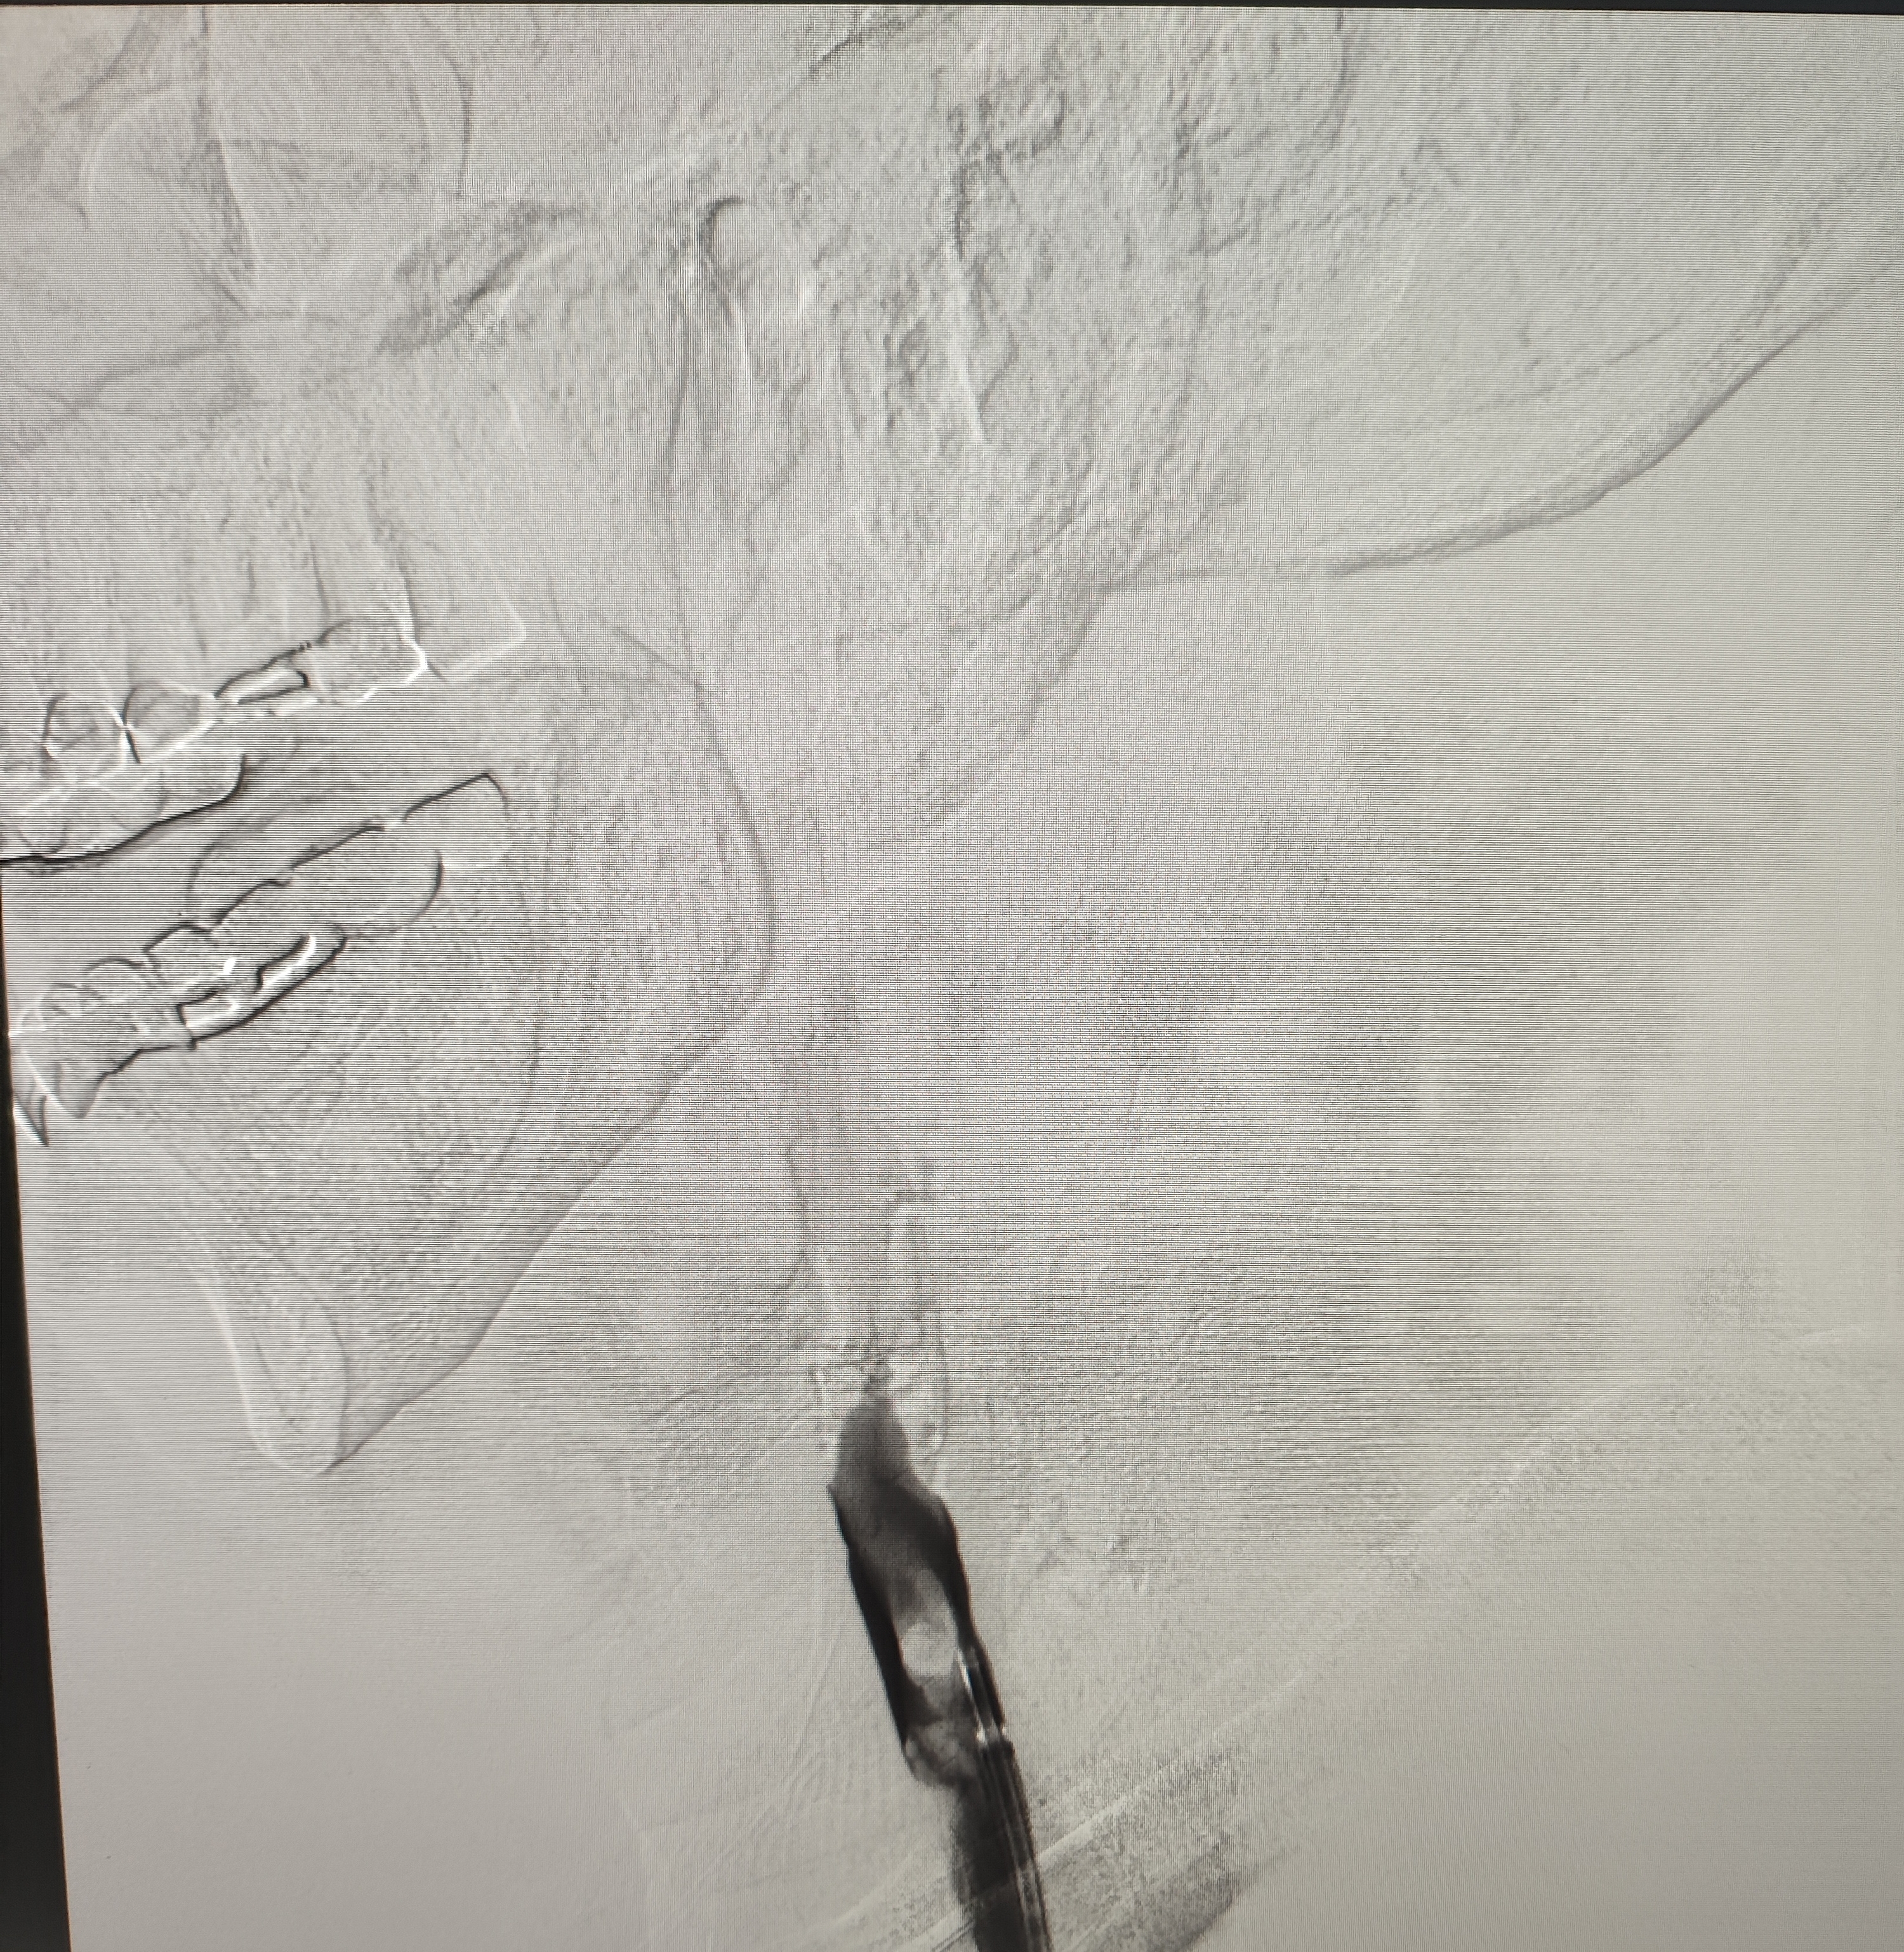

颈总巨大斑块急性闭塞的血管内治疗(双颈动脉支架桥接+支架释放后掉斑块,抽吸取栓)

急诊上台。